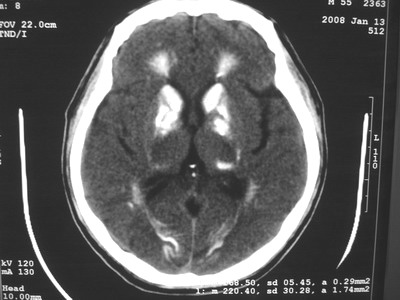

以下是引用随光逐影在2008-1-14 17:26:00的发言:[br]考虑为:甲状旁腺功能低下。需与fahr`s病相鉴别。建议:实验室检查。